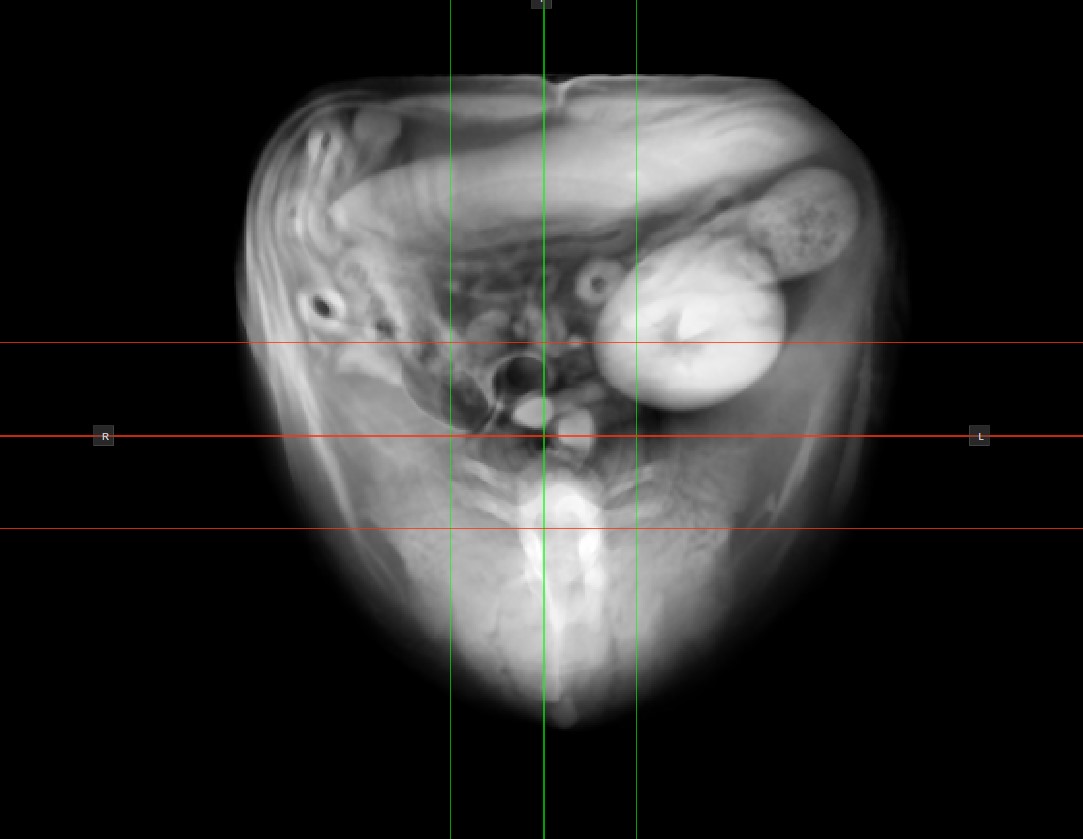

The active thick slab mode in the CT Viewer can be modified by choosing an option from the Thick Slab dropdown located in the bottom panel of the viewer.

Modify the slice thickness by dragging the Value slider in the desired direction, or enter a specific value in the input field. The slicers will correspond to the chosen value and they will spread out to indicate the current thickness.